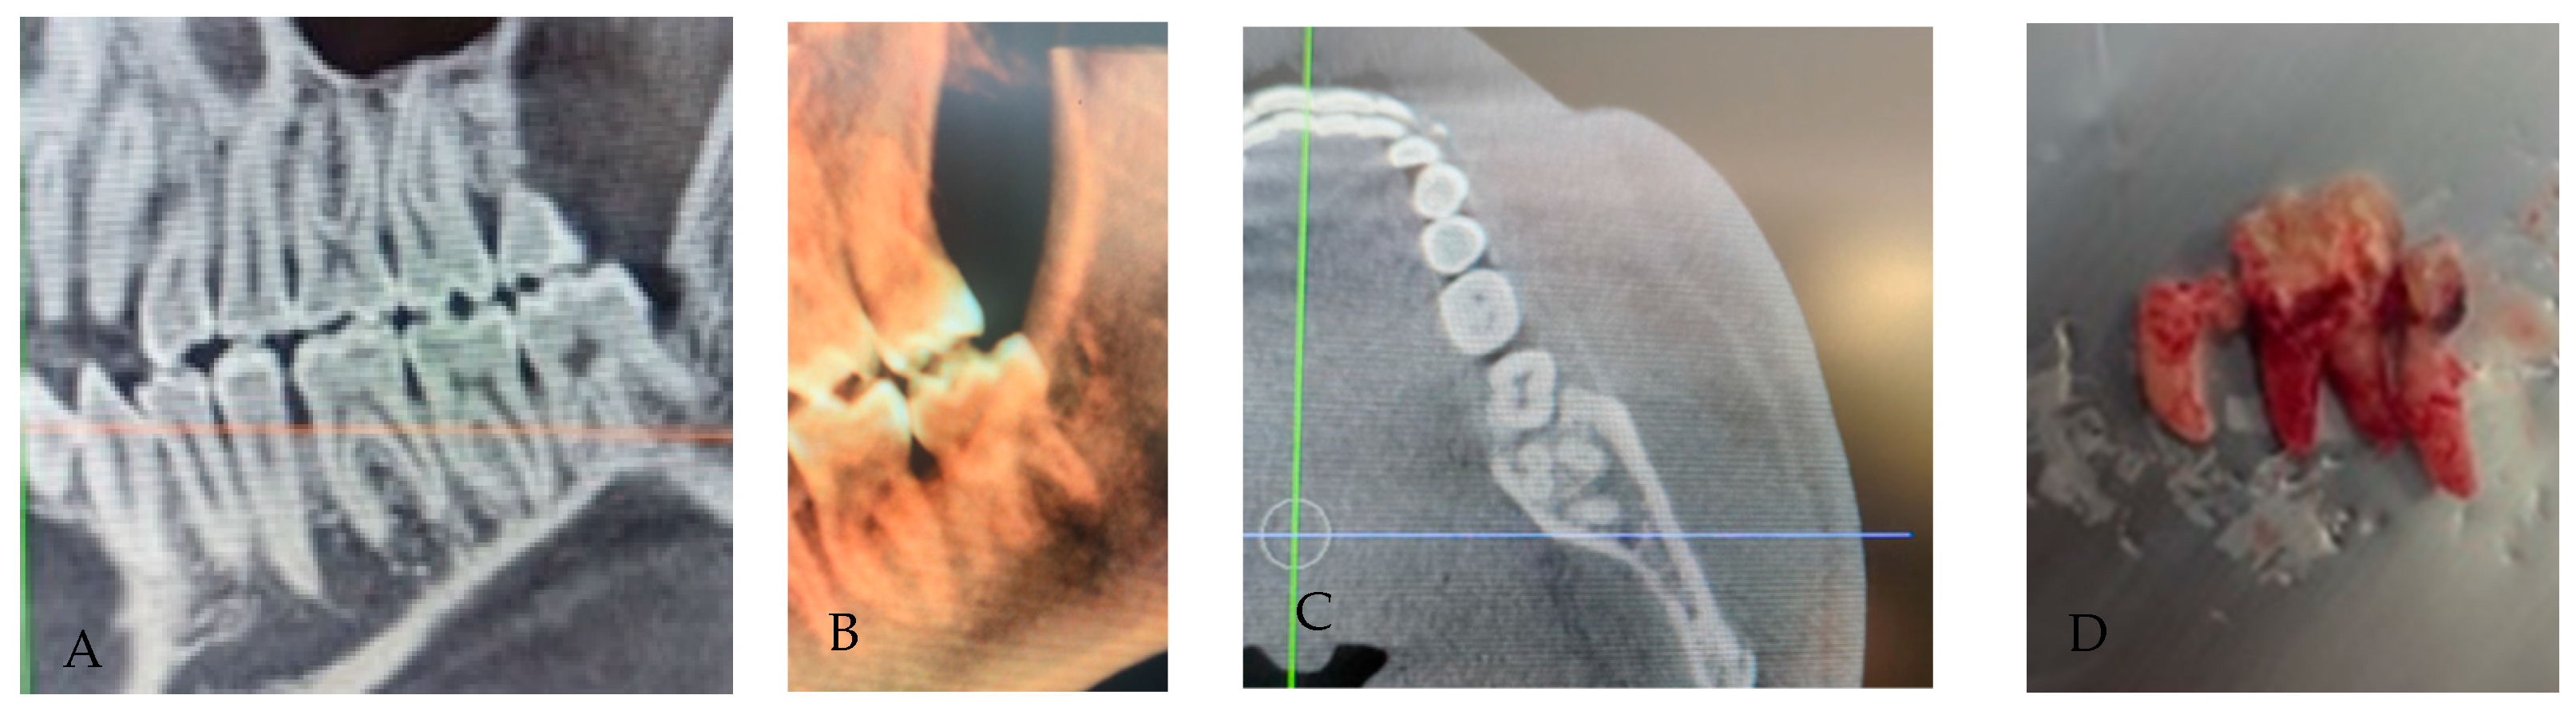

3.2. Radix Entomolaris

- Type I: straight root/canal;

- Type II: curvature in the coronal third, followed by a straight continuation;

- Type III: curvature in the coronal third with an additional buccal curvature in the apical third.

3.3. Radix Paramolaris

3.7. Dilaceration/Apical Curvature